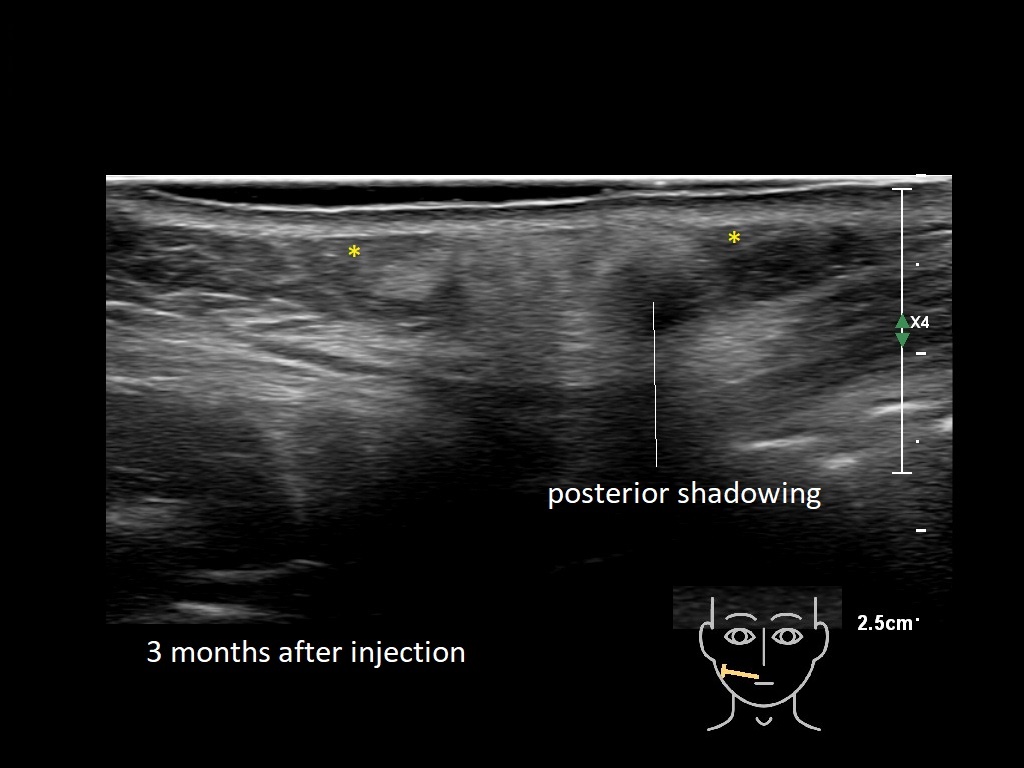

Draw in the image on the right where the fillers are located. To check if your answer is correct, please click on the secondary image.

Fillers

Draw in the second image below where the fillers are located. To check if your answer is correct, swipe the first image to the right.